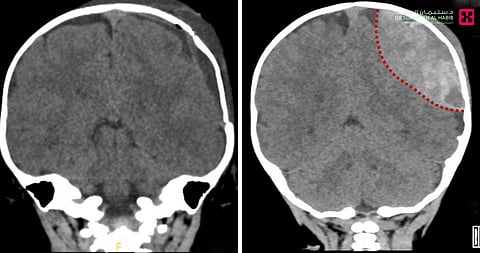

وقال د. حسنين الحاصل على البورد الفرنسي أن الطفل أسعف إلى المستشفى الساعة الثانية صباحاً، بعد معاناة مع نوبات استفراغ متلاحقة، وتراجع في مستوى الوعي، وفور وصوله تلقى العلاجات الأولية، ومن ثم أخضع لعدة فحوصات دقيقة، أبرزها أشعة C.T- scan للرأس، التي بينت نتائجها وجود كسر في الجمجمة، بالإضافة إلى نزيف داخلي كون تجمعاً دموياً ضخماً شكل ضغطاً كبيراً على المخ.

حيث أجريت له عملية في الثالثة صباحاً تحت التخدير العام، عن طريق فتح جلد الرأس والجمجمة وإزالة الدم المتجمع برفق ودقة شديدة، ووقف النزيف الدموي وإصلاح كسر الجمجمة وإعادة العظم إلى وضعه الطبيعي بنجاح تام، واستغرقت العملية نحو ساعة ونصف الساعة، وتكللت جهود الفريق الطبي ولله الحمد بنجاح كبير، ونُقل الطفل إلى العناية المركزة بحالة مستقرة، قبل أن يتم تحويله بعد 48 ساعة إلى غرفة تنويم عادية، وتحسنت صحة الطفل باضطراد مع العناية الطبية الحثيثة إلى أن غادر المستشفى بعد "4" أيام من العملية وهو بحالة صحية جيدة، وقد تخلص من كافة الأعراض التي قادته إلى المستشفى.